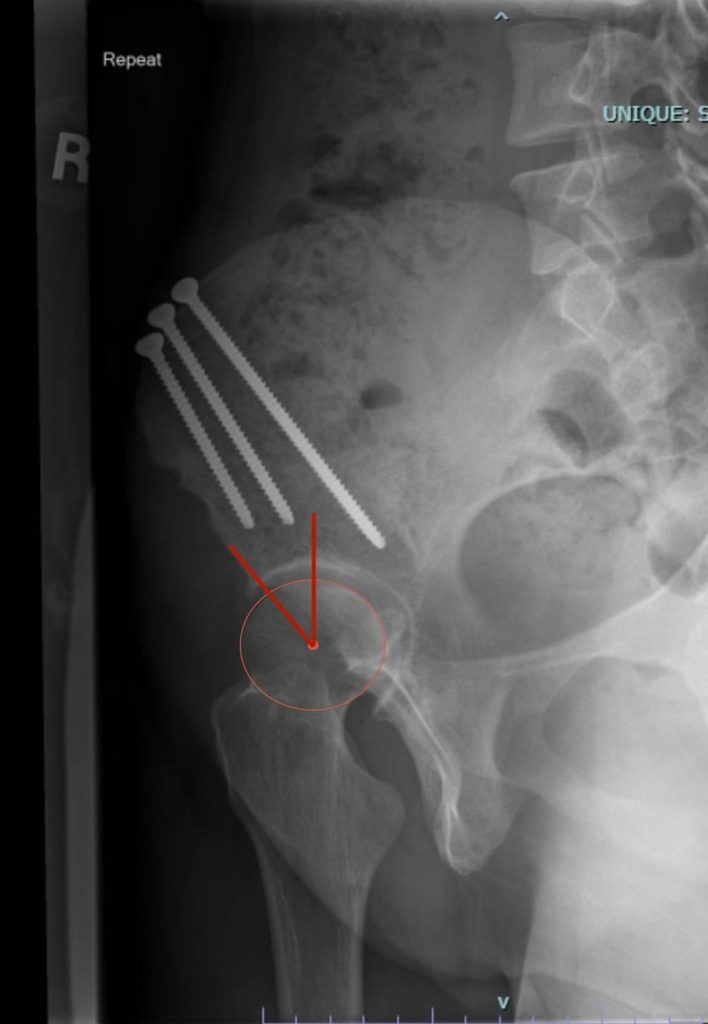

Alpha Angle

The head of the femur should round. The alpha angle measures how much the shape of the femoral head differs from the normal spherical shape.

> 55 degrees is associated with CAM morphology that can be seen in femoroacetabular impingement and hip dysplasia. Notice how there is extra bone outside the circle (red arrow).